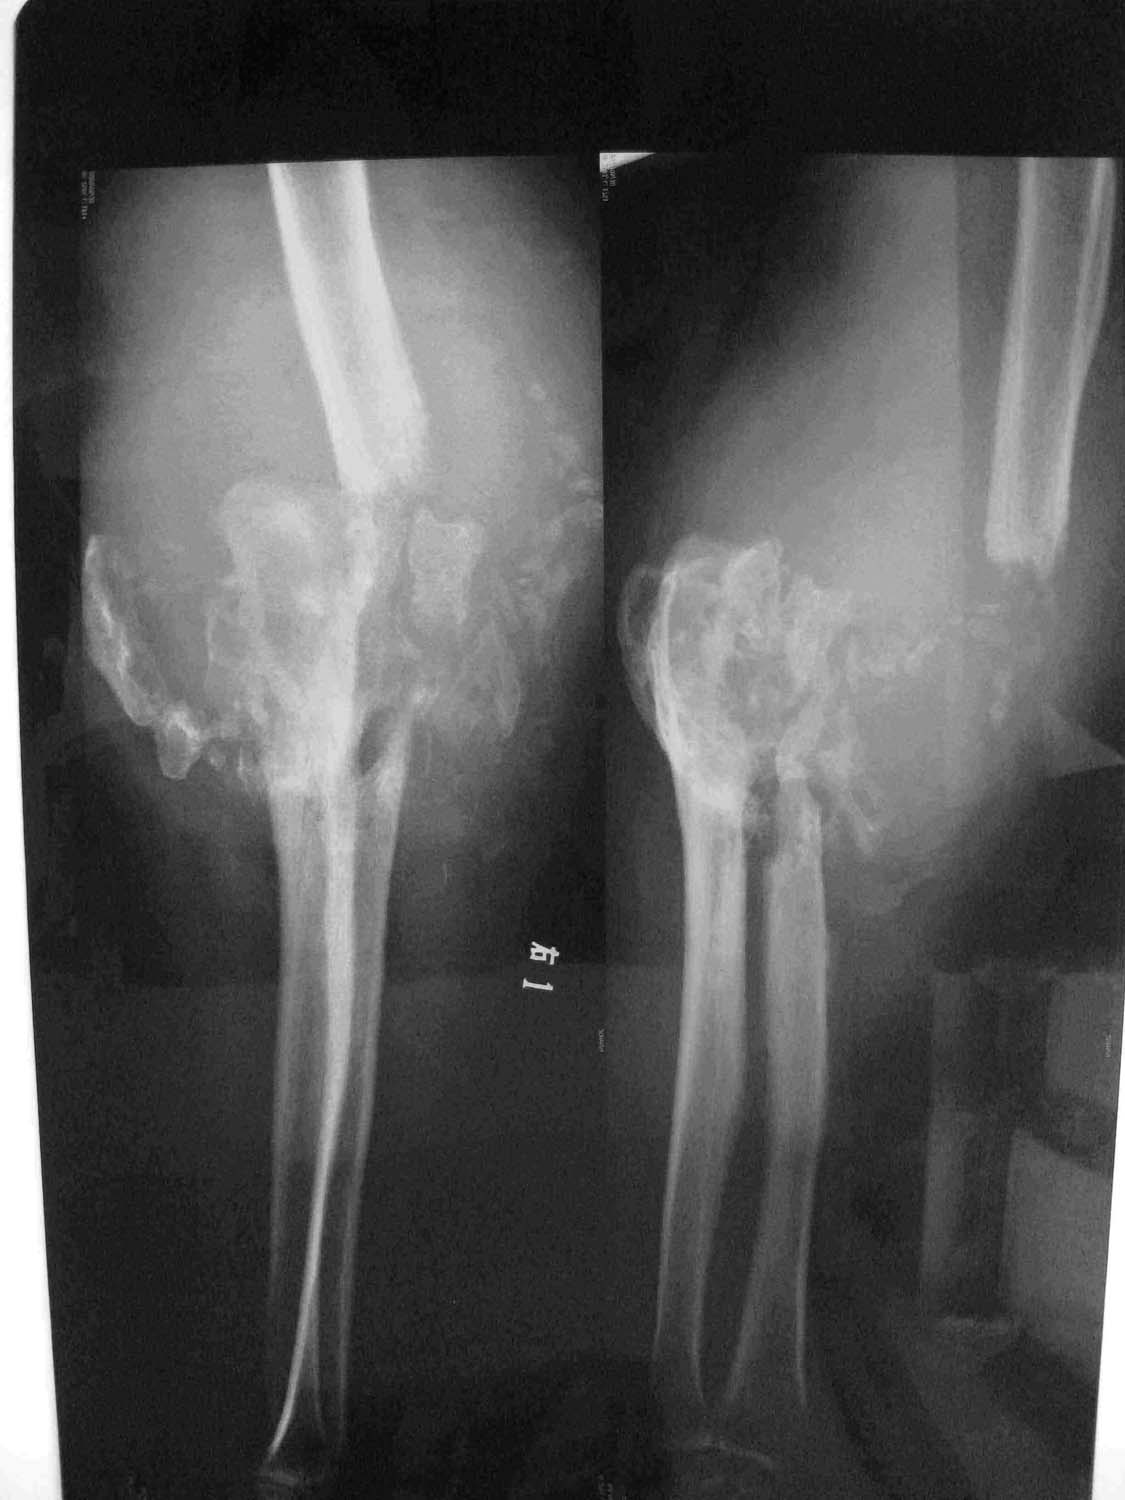

患者男性,57岁,主因右上肢肿物10年,突然加重伴发热10天入院。患者10年前无意中发现右前臂肿胀,无明显发热及疼痛,较对侧增粗。10余年无明显不适,无缓慢增长,不伴地热及盗汗,无皮肤红肿,自诉在当地行拍片检查未发现骨质异常,未曾治疗。10天前肿物突然出现增大,轻度发热,皮温增高,无手部麻木无力,无皮肤破溃。来院。患者自病情加重查体以来饮食差、消瘦,睡眠及二便正常。既往体健,无结核发病及接触史。5年前右手掌部感染,当地手术治疗,遗留右手屈曲挛缩畸形,功能丧失。查体:体消瘦,t:37.4摄氏度。右上肢明显肿胀,皮下深处质硬肿物,边界清楚,可轻度移动,轻度压痛,局部皮温增高,有波动感,右手肘、腕及各手指已完全丧失活动。

相关化验:c反应蛋白 56.8mg/l   ,  bun:2.42mmol/l  , alb:23.3g/l , glo:36.9g/l  ,hgb:76.4g/l , esr: 82mm/h。

影像学表现:关节不稳定,脱位,显著的关节渗出,关节骨端骨部分吸收,残余骨密度居正常或增加,周围软组织明显肿胀、规则钙化或碎骨片。

轻微的自觉症状和严重的x线极不相称是诊断本病的要点。

患者肘关节骨端广泛破坏、硬化且呈奇异形态,关节病理性脱位,周围软组织钙化,骨碎片,结合患者病程中无明显疼痛。近10天症状加重。综合上述几点考虑为夏科氏关节也称神经性关节炎,并发感染。